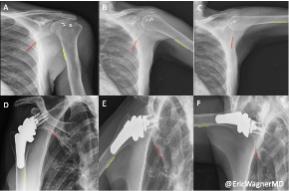

Emory Healthcare researchers published a study using Dynamic Digital Radiography (DDR) to compare shoulder biomechanics in patients after two widely accepted surgical interventions for massive irreparable rotator cuff tears (MIRCTs). Reverse shoulder arthroplasty (RSA) and arthroscopically assisted lower trapezius tendon (aLTT) transfer are often used to repair these tears, however, quantifying shoulder function post-operatively has remained difficult to assess. However, with the use of novel DDR imaging, it provided the ability to examine in-vivo kinematics by measuring scapulohumeral rhythm (SHR), the ratio of the glenohumeral and scapulothoracic contributions to shoulder motion, non-invasively in patients. The authors also aimed to design an objective methodology for selecting the appropriate intervention that will maximize the patient’s shoulder mobility with the help of DDR. The study is available online in the Journal of Shoulder and Elbow Surgery.

DDR is a novel, low-dose X-ray imaging technique available on Konica Minolta Healthcare DR Systems that captures both static images and cinegrams, providing an innovative way to obtain detailed images of complex joints like shoulders while in motion. By acquiring a series of images at high speed, DDR generates a cineloop that enables clinicians to visualize anatomical motion over time (cineradiography), enhancing the system’s diagnostic capabilities. Utilizing DDR to characterize scapulohumeral rhythm both pre- and post-operative and evaluate for precise changes in SHR, Sameer R. Khawaja, MD, and collaborators, including the leadership of Eric R. Wagner, MD, MSc, and his research lab, demonstrate that Dr. Wagner’s patients undergoing aLTT yields superior restoration of shoulder biomechanics for patients suffering from MIRCTs than his

patients undergoing RSAs. The study highlights how aLTT transfer enhances shoulder stability and improves functional mobility. In contrast, RSA is a very successful treatment of MIRCTs and other pathologies but fails to restore the same level of native biomechanics as the aLTT.

“Using the dynamic radiography provided by Konica Minolta’s DDR imaging enables us to change the clinical algorithms for both preoperative decision making and postoperative evaluations of surgical outcomes,” says Dr. Wagner.

“It’s often difficult to decide whether we should do a RSA or aLTT for these patients with massive rotator cuff tears. These are very different treatments,” says Zaamin Hussain, MD, Orthopedic Surgery Resident, Emory Healthcare. “Not only can the DDR images help make that decision preoperatively, but the results of this study suggest there is potential for improved overall coordination of the shoulder with aLTT, which is only possible to assess with in vivo dynamic imaging!”

“Konica Minolta congratulates the team at Emory Healthcare on the publication of their study demonstrating the clinical utility of DDR in comparing post-surgical outcomes in patients undergoing reconstructions for MIRCTs,” says John Sabol, PhD, Clinical Research Manager, Konica Minolta Healthcare. “DDR is an FDA cleared radiography solution that provides valuable insight into the dynamic relationship of bones and soft tissue through their full range of motion. As the Emory team has demonstrated in this work, DDR overcomes the historical challenges in evaluating biomechanics in clinical patient populations. This will enable improvements in the quality of care and patient outcomes.”